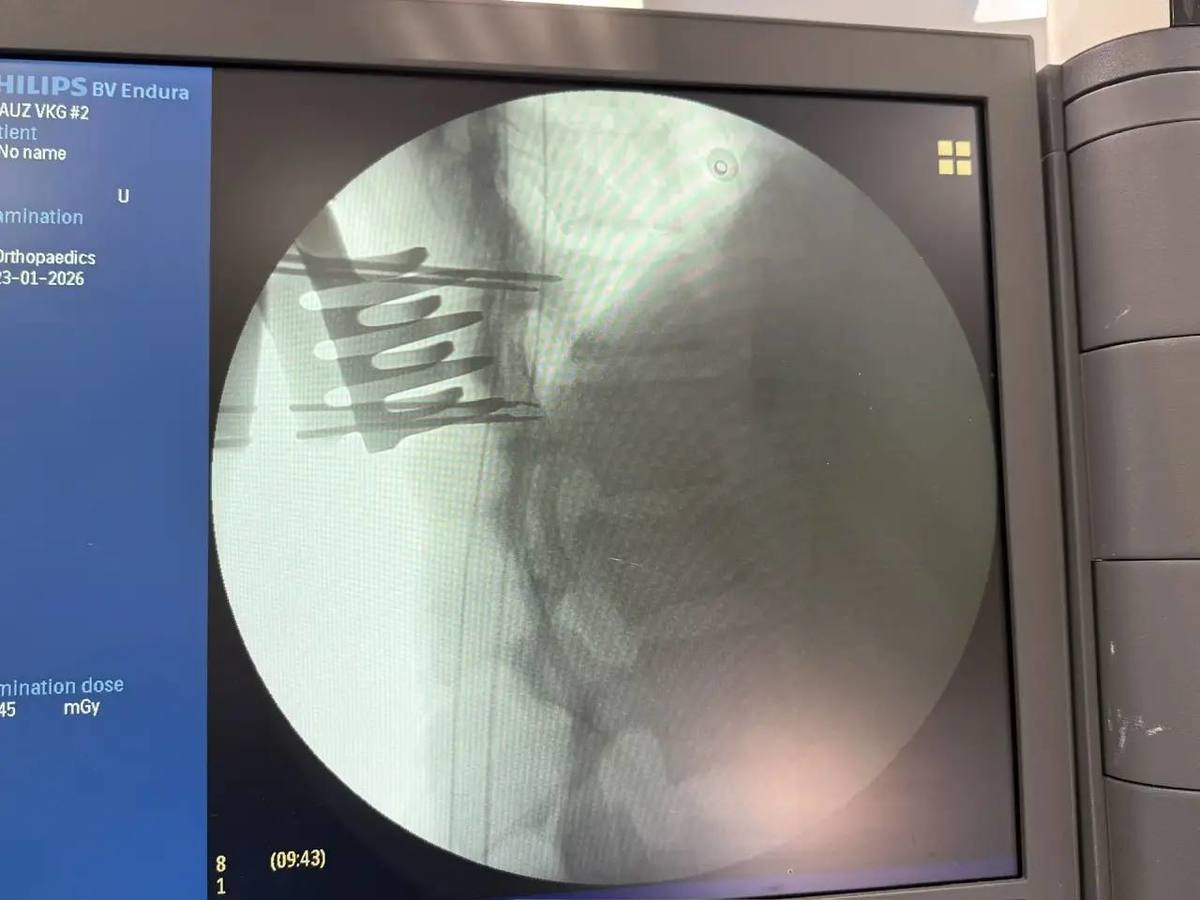

В Тысячекоечную больницу 19 января из Арсеньева была доставлена 18-летняя девушка с диагнозом «компрессионный перелом тела позвонка со стенозом позвоночного канала». Травма привела к сдавливанию спинного мозга, что вызвало неврологический дефицит (парез ног) и нарушение функций тазовых органов. Нейрохирурги провели сложное 4-часовое вмешательство и в итоге сделали всё, чтобы травма осталась только в прошлом. Сейчас девушка выписана на амбулаторное лечение.